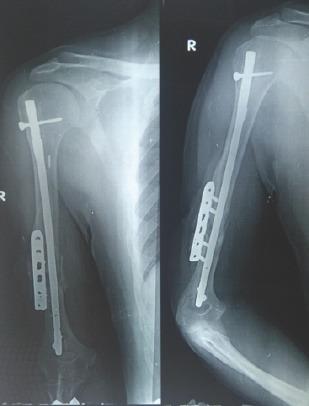

We report a case of a young adult male who sustained a compound fracture of humerus shaft treated with intramedullary nailing followed by subsequent bone grafting and eventually landed up in non-union and was treated at our center by locking compression plate application with nail in situ with iliac crest autogenous bone graft followed by shoulder spica application.

我们报告一例年轻成年男性病例,其肱骨干发生开放性骨折,接受了髓内钉固定治疗,随后进行了骨移植,最终出现不愈合,并在我们中心接受治疗,采用锁定加压钢板原位固定并加用髓内钉,取自体髂骨移植,随后应用肩人字石膏。